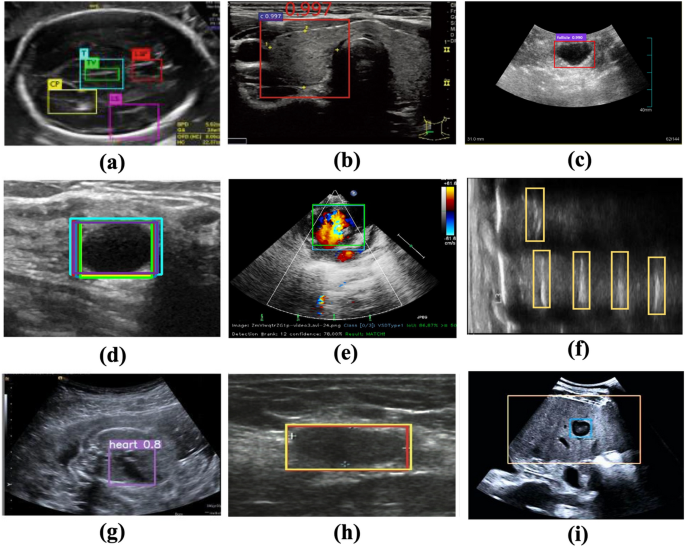

The application of DL object detection technology in ultrasound image analysis has been increasing, and various DL models have been proposed (Fig. 2). In 2018, Lin et al. located 5 anatomical structures within the fetal head ultrasound image using the Faster R-CNN method26. Li et al. modified the structure of Faster R-CNN to detect the thyroid papillary carcinoma in ultrasound images27. In 2019, Zeng and Liu adjusted the Faster R-CNN structure to detect cattle ovarian follicle in the follicle ultrasound image28. Cao et al. compared multiple DL object detection models on breast lesion detection29. In 2021, Chen et al. modified the single-stage detector YOLOv4 to recognize the ventricular septal defect in echocardiographic images30. Bassiouny et al. compared Faster R-CNN and RetinaNet in discriminate lung ultrasound feature31. Besides, Faster R-CNN and YOLOv5 models were also applied in detecting breast nodules and recognizing fetal anatomical plane32,33. Recently Dadoun et al. tried the DETR to locate the focal liver lesions in abdominal ultrasound image, and the performance of DETR preceded the Faster R-CNN34. It could be seen that Faster R-CNN or YOLO series models are relatively popular and different types of models are needed to be compared to select the most suitable model.

Object detection in ultrasound image analysis. (a) Fetal standard transthalamic plane26. (b) Thyroid papillary carcinoma27. (c) Cattle ovarian follicle28. (d) Breast benign lesion29. (e) Ventricular septal defect in echocardiographic image30. (f) Lung ultrasound feature31. (g) Anatomical plane in fetus32. (h) Breast nodule33. (i) Focal liver lesion34.

One notable difference between traditional object detection problem and the sampling position selection, is that patterns of human/animal faces are usually specific and distinct with the natural background (Fig. 2). However, area of the sampling position can be similar to its surrounding region belonging to the same artery. The selection of sampling position relies on the physician’s comprehensive analysis and clinical experience, which is a challenge for the model construction and predictive accuracy of DL object detection technology.